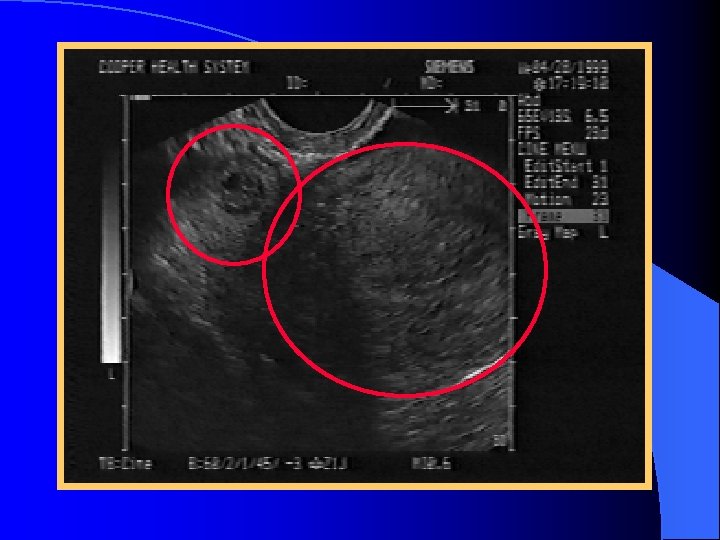

Adenexal Mass

Sonographic Spectrum of EP l Ruptured ectopic pregnancy l Definite ectopic pregnancy l Extrauterine empty gestational sac l Adenexal mass l Pseudogestational sac l Empty uterus

Definite Ectopic Pregnancy A thick, brightly echogenic, ring-like structure located outside the uterus with a gestational sac containing an obvious fetal pole, yolk sac or both.

Extrauterine Gestational Sac Extra-uterine mass containing a thick, brightly echogenic ring surrounding an anechoic area l Brightly echogenic appearance may be helpful l Tubal ring l